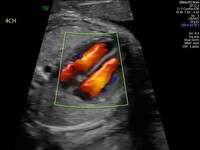

Οι συγγενείς διαμαρτίες της καρδιακής διάπλασης εμφανίζονται σε ποσοστό 0.08 - 1% των ζώντων νεογνών με υψηλότερο ποσοστό στα έμβρυα. Συνήθως πρόκειται για δομικές ανωμαλίες όπως ενδοκαρδιακές επικοινωνίες, στενώσεις ή ατρησία βαλβίδων, υποπλασία κοιλιών ή ανωμαλίες των μεγάλων αγγείων. Ένα μικρό ποσοστό παιδιών γεννιούνται με αρρυθμίες, κυρίως διαταραχές αγωγιμότητας και υπερτροφική ή διατατική μυοκαρδιοπάθεια, αν και τα τελευταία συνήθως παρουσιάζονται αργότερα στην παιδική ηλικία ή στην ενήλικο ζωή. Το ποσοστό της προγεννητικής διάγνωσης κυμαίνεται από 30-70% και η μεγάλη διακύμανση στο ποσοστό αυτό έχει να κάνει με την εμπειρία του εκάστοτε ιατρού, τον τεχνολογικό εξοπλισμό, τη διάρκεια της υπερηχογραφικής μελέτης καθώς και με το BMI (δείκτης μάζας σώματος) της ασθενούς.

Η προγεννητική διάγνωση των συγγενών καρδιοπαθειών έχει καθιερωθεί τα τελευταία 40 χρόνια και σε εξειδικευμένα κέντρα και επιτυγχάνεται με τη μεγαλύτερη δυνατή διαγνωστική ακρίβεια. Πραγματοποιείται στις 18-20 εβδομάδες κύησης, ενώ για κυήσεις υψηλού κινδύνου ο πρώτος υπέρηχος καρδιάς εμβρύου μπορεί να πραγματοποιηθεί ήδη από τις 12-14 εβδομάδες κύησης. Από τη στιγμή που θα γίνει η διάγνωση μιας συγγενούς καρδιοπάθειας ενημερώνονται οι γονείς για την καρδιακή πάθηση, για τη διαθέσιμη θεραπεία, τη θνητότητα και τη θνησιμότητα καθώς και για την ποιότητα ζωής του παιδιού στο μέλλον. Σε επιλεγμένες περιπτώσεις υπάρχει η δυνατότητα προγεννητικής παρέμβασης. Το πλεονέκτημα της υπερηχογραφίας και διάγνωσης από το πρώτο κιόλας τρίμηνο δίνει τη δυνατότητα για έγκαιρη και ασφαλή διακοπή της κύησης σε περιπτώσεις σοβαρής, μη συμβατής με την ζωή, συγγενούς καρδιοπάθειας καθώς και επαρκή χρόνο για χρωμοσωμικό έλεγχο και γενετική συμβουλή.